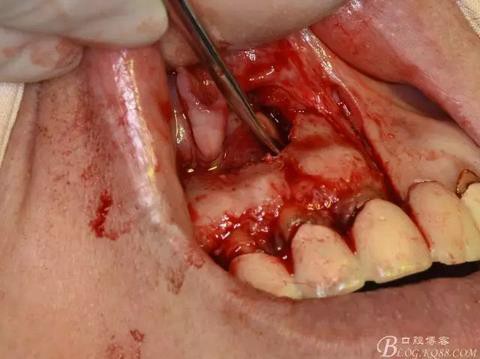

圖7. 分別在13的遠(yuǎn)中和11的近中做垂直切口加齦溝內(nèi)水平切口,形成梯形瓣

圖8.翻開梯形瓣

圖9.去除唇側(cè)薄的骨壁,暴露出囊壁